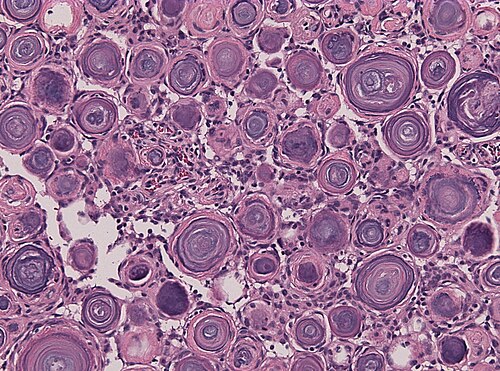

Exision of dura-based, calcified tumor.

High magnification

Higher magnification. H&E stain.

These round, calcified structures look like Psammoma bodies.

Psammomatous meningioma, WHO grade I

Comment: It is said, that psammoma bodies represent a process of dystrophic calcification or as an active biologic barrier to tumor spread ultimately leading to degeneration/death of tumor cells. [1] [2]